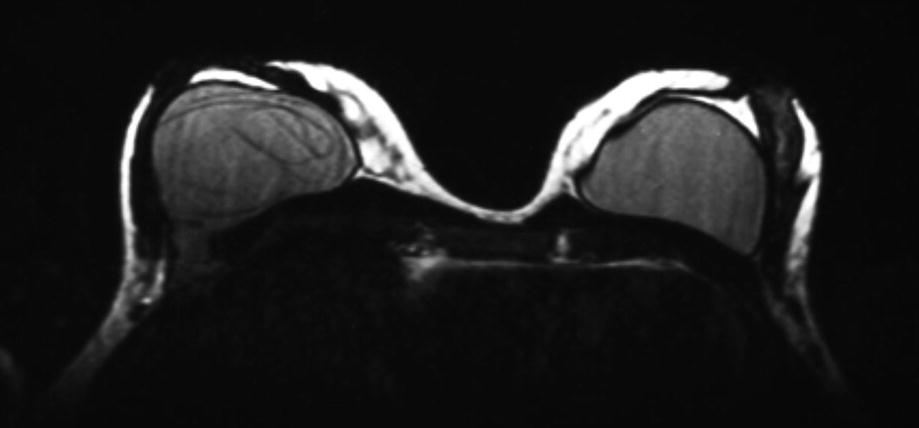

Magnetic resonance imaging (MRI) demonstrates both intracapsular and extracapsular prosthesis rupture and silicone leakage. (Courtesy of Dr. Román Rostagno)